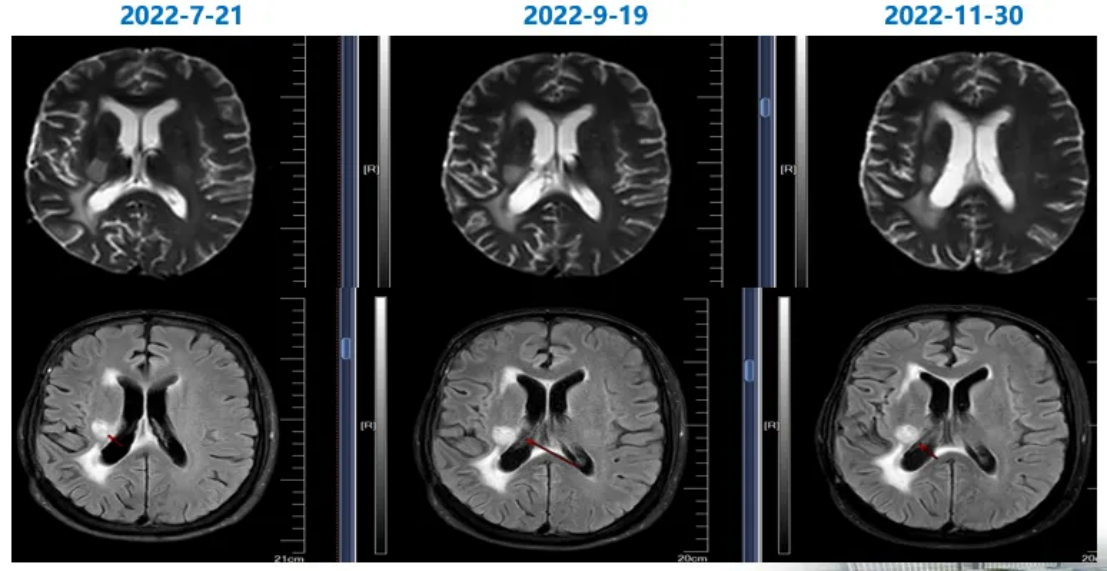

2022-9-19脑部MRI随访复查:右侧颞叶胶质瘤术后,右侧额叶侧脑室前角旁结节,右侧基底节区后部片状异常信号,较前(2022-7-1)强化程度减低;右侧脑室周围及胼胝体压部缺血灶,较前片相仿;右侧额颞部少许硬膜下积液,较前稍吸收;右侧基底节区陈旧性腔梗灶(图5)。

2022-11-30脑部MRI随访复查:右侧颞叶胶质瘤术后,右侧额叶侧脑室前角旁结节此次未见,右侧基底节区后部片状异常信号,较前(2022-09-19)强化程度减低;右侧脑室周围及胼胝体压部缺血灶,较前片相仿;右侧额颞部少许硬膜下积液,较前相仿;右侧基底节区陈旧性腔梗灶(图5)。

2023-1-28脑部MRI随访复查:右侧颞叶胶质瘤术后,右侧基底节区后部片状异常信号,较前(2022-11-30)范围基本相仿,建议定期复查;右侧脑室周围及胼胝体压部缺血灶;右侧额颞部少许硬膜下积液,较前相仿;右侧基底节区陈旧性腔梗灶(图5)。

2023-3-28脑部MRI随访复查:右侧颞叶胶质瘤术后;右侧基底节区后部片状异常信号,较前(2023-1-28)范围基本相仿,建议定期复查;右侧侧脑室周围及胼胝体压部缺血灶;右侧基底节区陈旧性腔梗灶(图5)。

图5靶向+替尼泊苷治疗前后脑部MRI图像